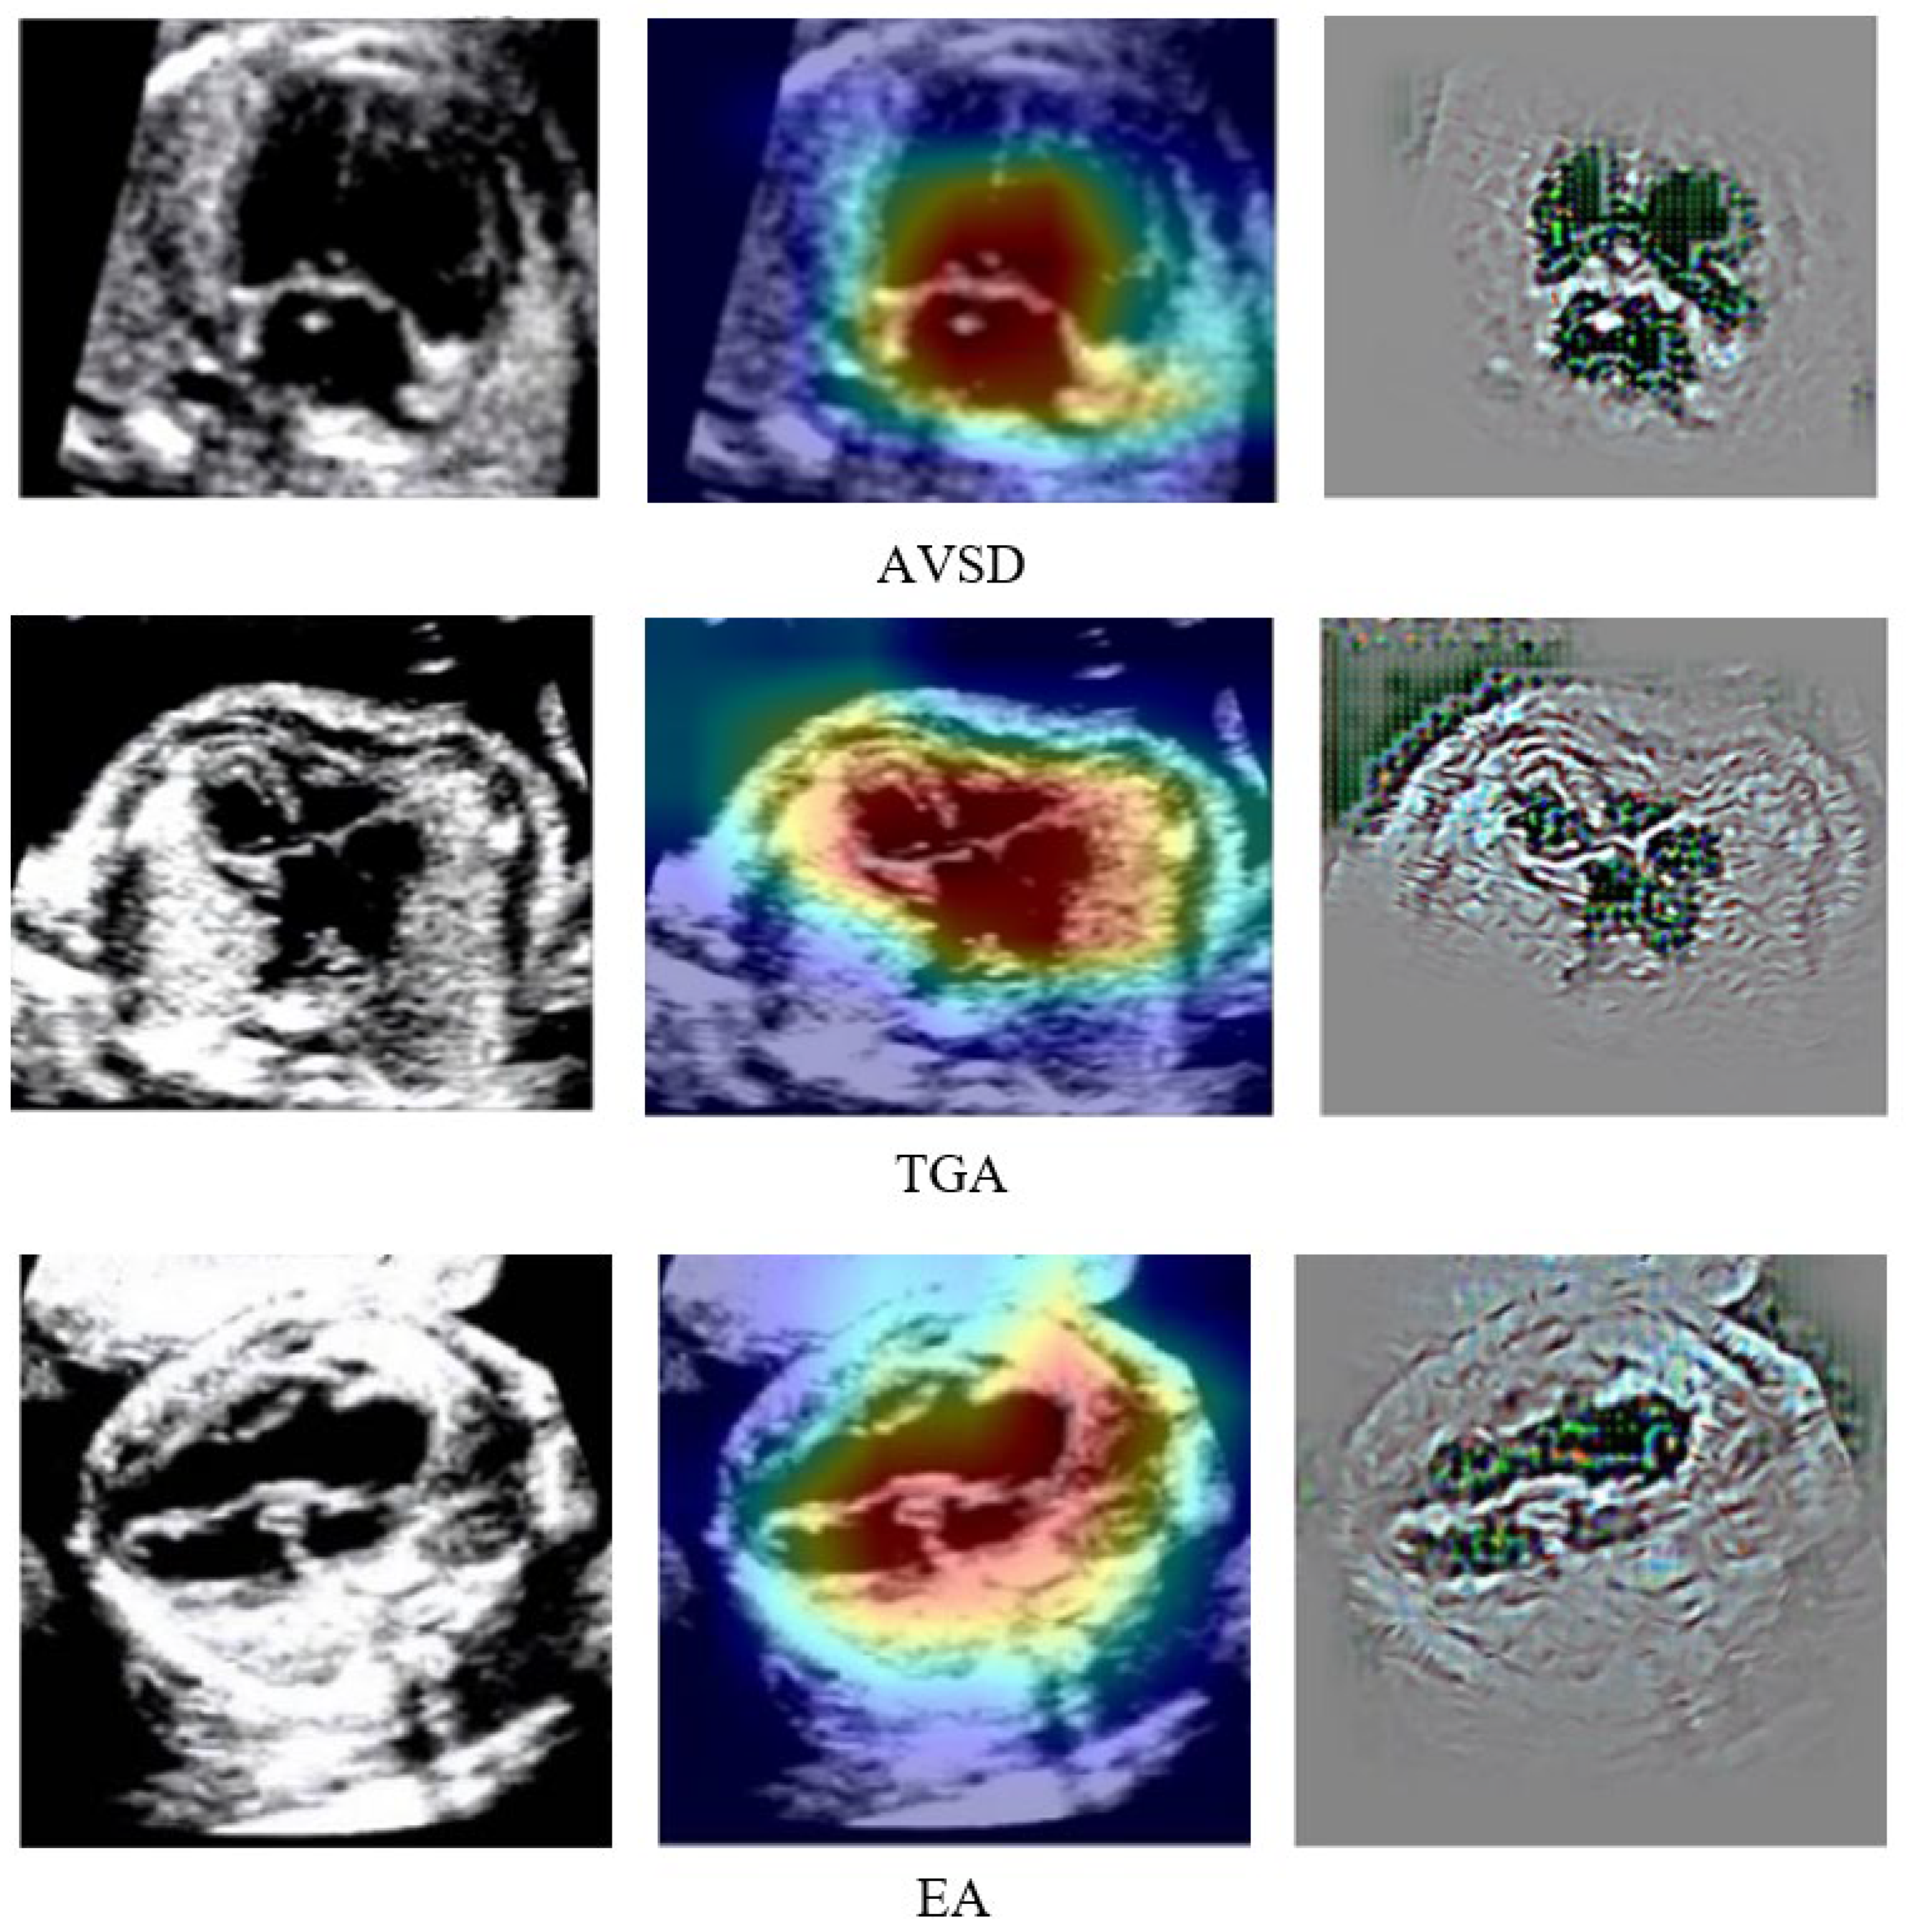

To explain the results of DenseNet201 classification so that they can be easily understood medically, we created a visualized image output after the classification process. A combination of guided backpropagation (Guided–BP) and gradient class activation mapping (Grad–CAM) was combined to describe abnormal pixels from US images as CHDs. Combining Guided–BP and Grad–CAM allowed us to generate sharp attributions. Class-discriminative visualization enables expert fetal cardiologists to understand where models are predicted. It can be used for any CNN-based model. A good explainable model should highlight fine-grained details in the image to visually explain why the model predicted a class. Such results can improve expert fetal cardiologists understanding from a medical point of view. Figure 8 depicts the raw image, Grad–CAM, and a combination of Guided–BP and Grad–CAM visualization. There was an excellent localization process for most of the images used in our experiment. Such visualizations can be used to inform downstream model enhancements.

Figure 8.

DenseNet201 Classification Result Explained by Guided–BP and Grad–CAM.